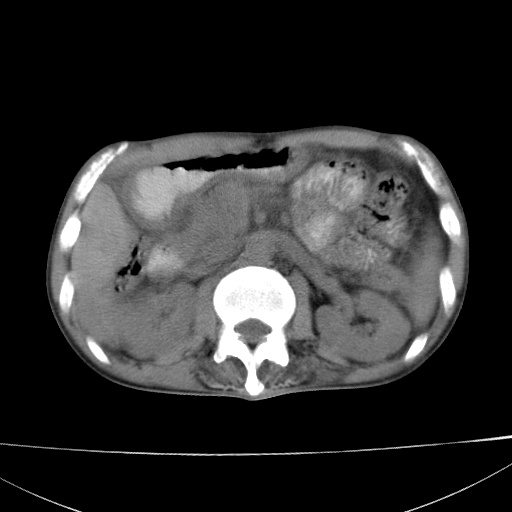

患者 男  41岁,右上腹痛伴腹泻10天,8年前有乙肝,本次b超查肝右叶占位来做ct ,请会诊!

肝硬化\\脾大\\门静脉高压,胃底静脉曲张可能性大.肝右叶肝癌肝内转移,建议增强.左侧小结石.

肝右叶肝癌肝内转移,建议增强

支持肝癌伴肝内转移,脾大,门静脉高压,胃底静脉曲张。

1)考虑肝癌;建议行ct增强扫描检查。2)脾大,门静脉高压,胃底静脉曲张。3)左肾小结石。

1)考虑肝癌及门脉瘤栓,建议行ct增强扫描检查。2)脾大,门静脉高压,胃底静脉曲张。3)左肾小结石。

结合病史;考虑肝癌。门静脉高压,脾大。胃底静脉曲张。

1)考虑肝癌;2)脾大,门静脉高压,胃底静脉曲张。3)左肾小结石。建议行ct增强扫描检查。